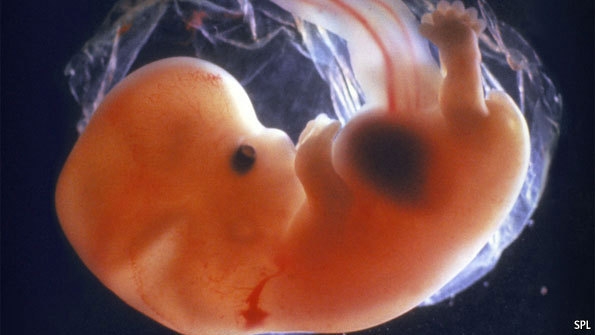

На протяжении первого триместра происходит активное формирование и развитие ключевых систем и органов будущего ребенка. Каждая неделя, начиная с момента зачатия, имеет огромное значение для малыша и представляет собой важный этап его роста. На седьмой неделе мы наблюдаем пятинедельный эмбрион, который пока еще не напоминает человека, но вскоре его контуры станут более узнаваемыми. В этот период активно развиваются нервная, дыхательная, пищеварительная и другие системы плода, формируются ручки и ножки, а также начинает функционировать сердечко.

С развитием головного мозга голова малыша продолжает увеличиваться и становится непропорционально большой по сравнению с телом. На этом этапе диаметр головы составляет 0,8 мм. Мозг, который является головным концом нервной трубки, уже разделен на пять мозговых пузырей, каждый из которых соответствует определенному отделу мозга. В эту же неделю нервная трубка начинает соединяться с внутренними органами через новообразованные нервные волокна.

На лице будущего малыша, которое уже начало приобретать некоторые очертания, можно заметить маленькие черные точки, из которых в дальнейшем сформируются глазки. На седьмой неделе также начинается формирование сетчатки и зрительных нервов из выпячивания на переднем мозговом пузыре.

Активно продолжается развитие пищеварительной системы. В передней части первичной кишки можно четко выделить глотку и пищевод, а также уже оформлен желудок. Строение печени улучшается, развивается поджелудочная железа. Средний отдел связывается с желточным мешком, а из задней части формируется прямая кишка и зачаток мочевого пузыря. Из органов дыхания, которые развиваются из переднего отдела первичной кишки, пока присутствует лишь трахея и зачатки будущих бронхов.

Развивается позвоночный столб, на котором формируется шея. Ручки малыша удлиняются и принимают лопаткообразную форму, опережая в развитии нижние конечности. В области таза еще можно заметить небольшой хвостик. Между ножками формируются половые валики, которые станут основой для половых желез ребенка.

К концу седьмой недели окончательно устанавливается маточно-плацентарный кровоток, что усиливает кровоснабжение плода. Плацента продолжает развиваться и становится более плотной, ее толщина достигает 1,1 см.

На этом сроке с помощью УЗИ-аппарата уже можно услышать биение маленького сердечка. Начиная с шестой недели беременности, частота сердечных сокращений будет увеличиваться и к концу седьмой недели достигнет 110 ударов в минуту.

Этот период, как и весь первый триместр, характеризуется формированием и развитием всех органов малыша и имеет огромное значение как для его дальнейшего внутриутробного развития, так и для всей его жизни. Поэтому крайне важно, чтобы первые недели беременности проходили успешно.